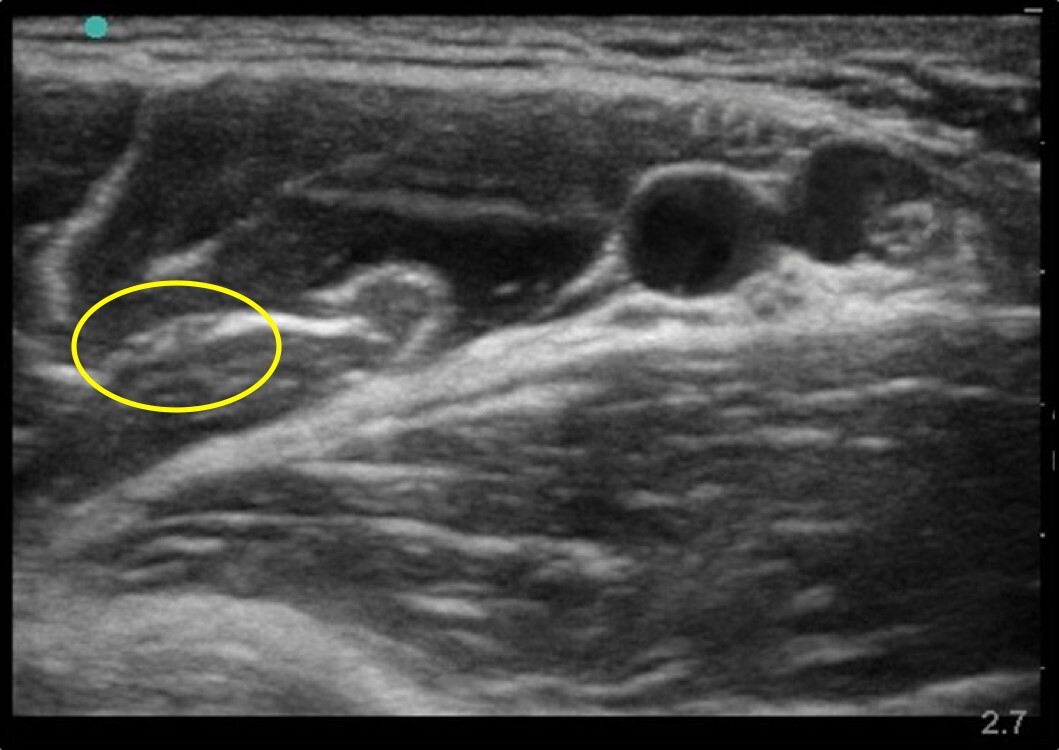

Musculocutaneous Nerve 3 Image

Circled: Musculocutaneous Nerve